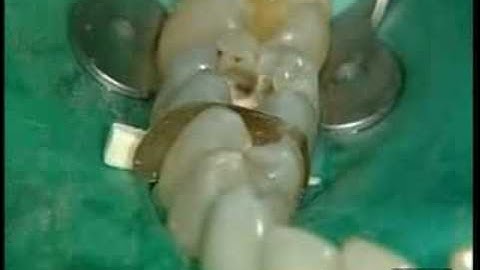

Universal flowable restorative Dr. P. Colon - X Flow /1